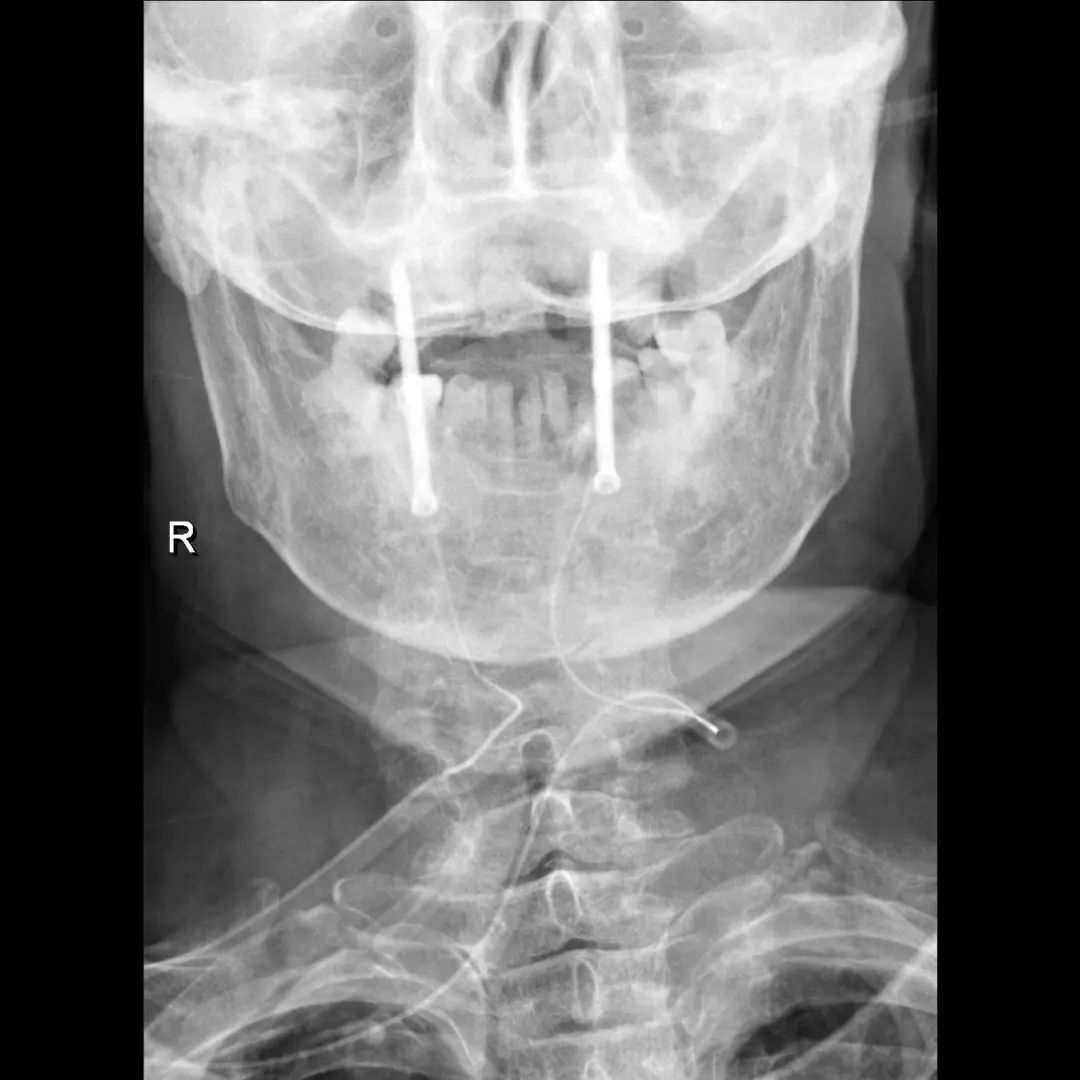

患者,男性,75岁,因外伤致颈部疼痛伴活动受限7天入院。患者入院前在当地医院确诊为:枢椎齿状突骨折Anderson-D’Alonzo分型Ⅱ型。

对于本患者来说,齿状突骨折后导致寰枢椎不稳,极易引起延髓或椎动脉损伤,严重者当场死亡。但患者同时合并严重胸腰椎后凸畸形,颈部后伸受限,不具备前路手术条件,这就给其治疗更增加了额外的困难。而由于手术部位延髓及椎动脉等血管神经密布,手术难度高、风险极大,稍有不慎,患者就会有生命危险。而患者家属在了解到手术的危险性后,曾自行到上级医院咨询专家,上级医院专家考虑围手术期死亡的风险,对于本例患者亦不愿提供手术治疗的机会。

患者经充分咨询了解,选择了枣庄市立医院脊柱外科主任王存平为其治疗。面对患者和家属期盼的目光,王存平明白这是患者最后的希望,故而没有胆怯和退缩,大胆提出了齿状突骨折后路切开复位C1、2椎弓根钉棒系统固定的手术方案。由于患者年龄较大,存在脊柱严重后凸畸形,俯卧位极度困难,全麻插管难度大,麻醉风险极大。麻醉科李传东和宓云飞医师克服重重困难,成功完成麻醉。在他们得力的麻醉和监护下,王存平仔细分离、细心操作,每一步都确保动作稳稳完成,最终成功实施了手术。

经过全程监护和系统治疗,患者术后恢复良好,骨折解剖复位,复查X线及CT显示固定位置佳,术后3天下地行走,术后4天即出院回家休养。